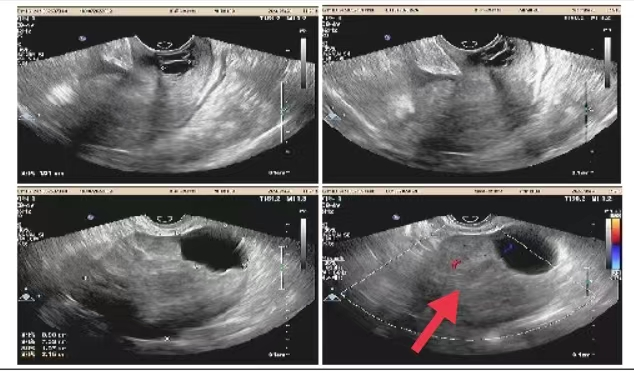

07**女士,65岁

2023年5月28日在邯郸仁泰北区体检,子宫附件彩超检查提示:子宫右上方见大小约8.9*7.4cm低回声团,内见范围约4.3*3.2cm液性暗区,CDFI:且见血流信号。考虑占位性病变,当日通知客户到三甲医院进一步检查,2023年6月10日跟踪回访,客户尚未检查,后连续三次跟踪客户均未检查,2023年8月1日又一次跟踪客户反馈已经检查考虑盆腔恶性肿瘤,家属还在纠结治疗方法,耐心讲解恶性肿瘤早期治疗的好处并劝说家属及时治疗,2023年9月1日再次回访,客户家属告知已完成手术,确诊为盆腔恶性肿瘤,并对仁泰体检专家对客户高度负责的状态表示感谢。